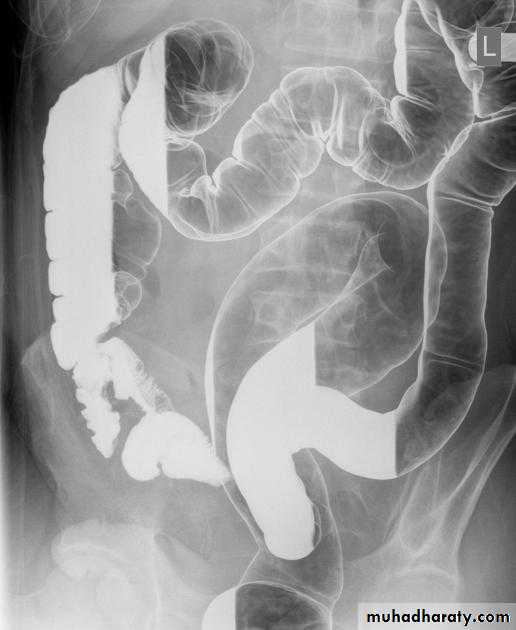

A barium follow-through procedure is a type of medical imaging technique. It is used to evaluate the presence of disease in a person's small intestine.Examination

Barium follow through x-rayThe patient drinks a contrast medium containing barium sulfate. This contrast medium appears white on x-rays, and shows the outline of the internal lining of the bowel. X-ray images are taken as the contrast moves through the intestine, commonly at 0 minutes, 20 minutes, 40 minutes and 90 minutes. This enables the radiologist to assess the bowel as it becomes visible. The test is completed when the Barium is visualised in the terminal ileum and Caecum, which marks the beginning of the large bowel. This is one of the most common places for pathology of the bowel to be found, therefore imaging of this structure is crucial. The test length varies from patient to patient as bowel motility is highly variable.

Radiological appearance of Mal absorption syndrome

* Loss of normal feathery appearance of the small bowel

* Flocculation & segmentation of the Ba

* Widening of the spaces between bowel loops due to mucosal edema

*+/_ spiky appearance of the small bowel loops